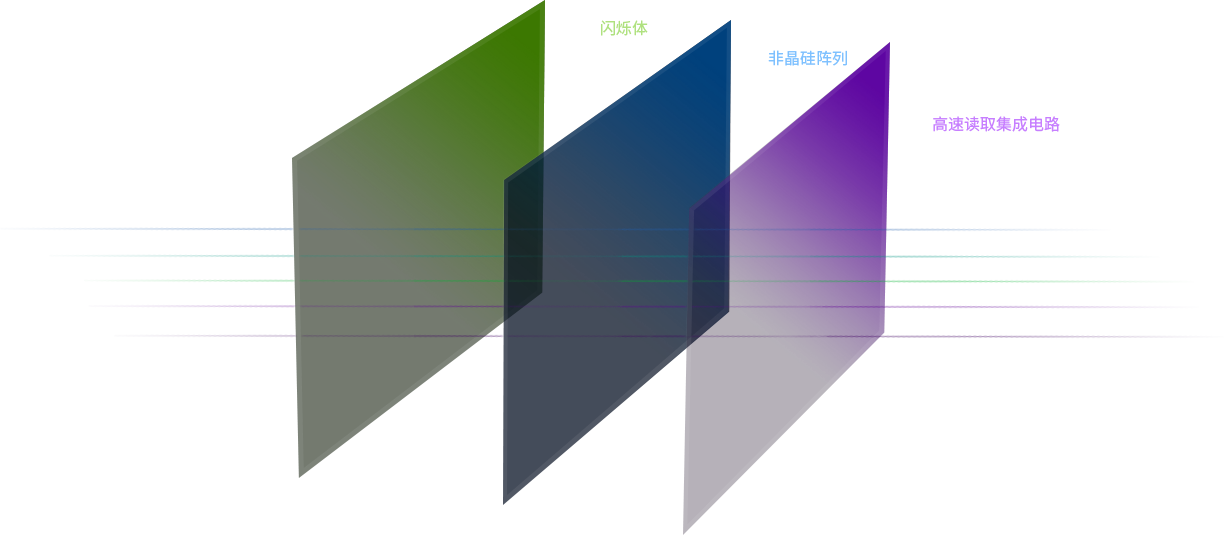

搭载超清大视野动态平板探测器,精准捕捉病灶,极致影像唾手可得,600微米碘化铯大幅提升X线转化效率,独特的非晶硅阵列与高速读取集成电路紧密协作,将实现多帧率透视与高清点片。